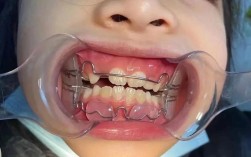

牙齿矫正金属矫正器,作为临床应用最广泛、历史最悠久的正畸装置,通过机械性外力引导牙齿移动至理想位置,是解决各类错颌畸形的重要手段,其核心结构由托槽、弓丝、结扎丝或橡皮圈组成,其中托槽通常由不锈钢或钛合金制成,通过专用粘接剂固定于牙齿唇颊面,...